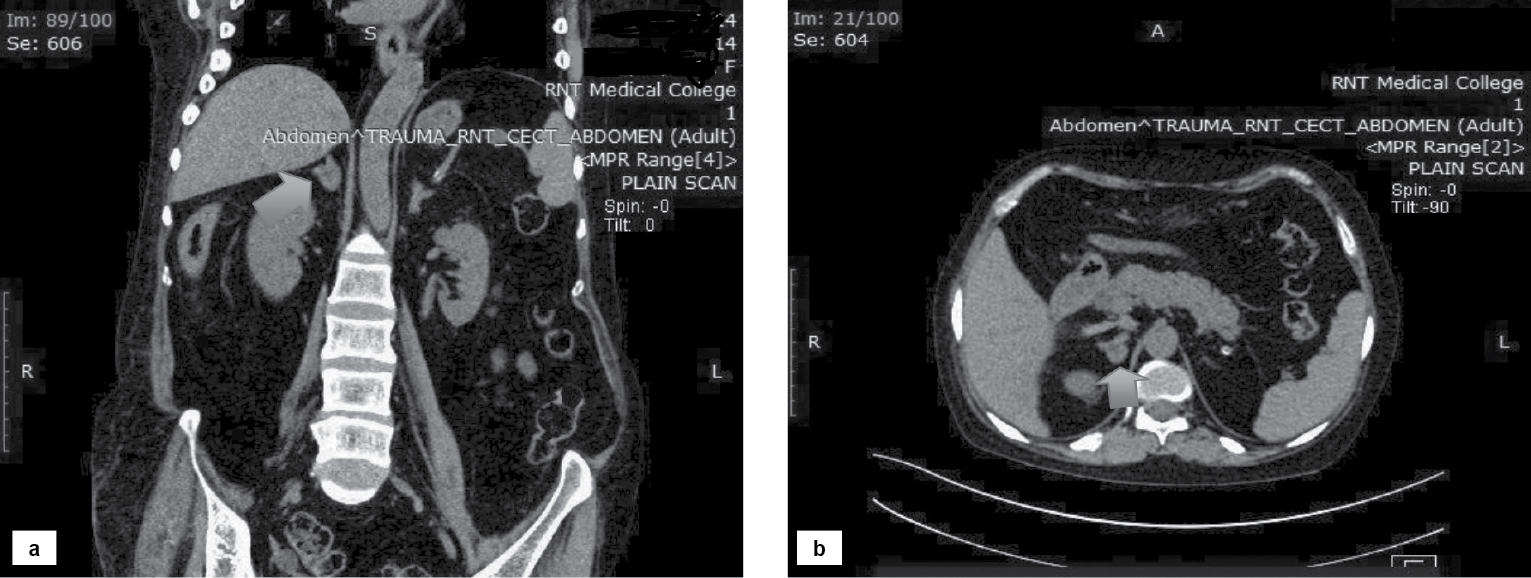

Computed tomography (CT) scan of the abdomen showed a soft tissue density lesion measuring 15 ´ 14 mm (Hounsfield Unit [HU] ~4-5) in the medial limb of the right adrenal gland (Fig. 3).

Figure 3. Coronal (a) and transverse (b) sections showing soft tissue density lesion in the medial limb of the right adrenal gland.